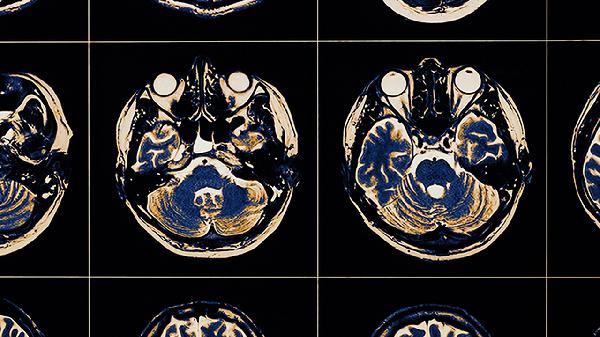

大脑脑萎缩可通过生活干预、物理治疗、药物治疗、手术治疗等方式治疗。脑萎缩可能与遗传、脑血管疾病、神经系统退行性变、外伤、感染等因素有关,通常表现为记忆力减退、认知功能障碍、运动协调能力下降等症状。